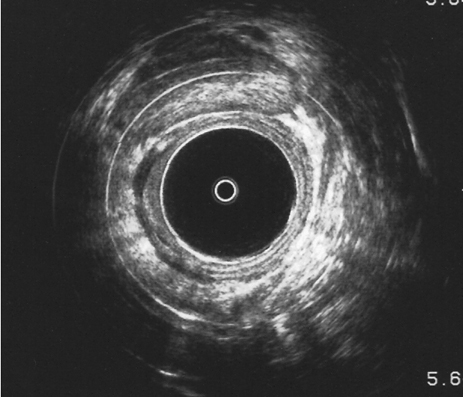

Ecografía rectal tras radioterapia en paciente con tumor rectal. Regresión tumoral e inflamación